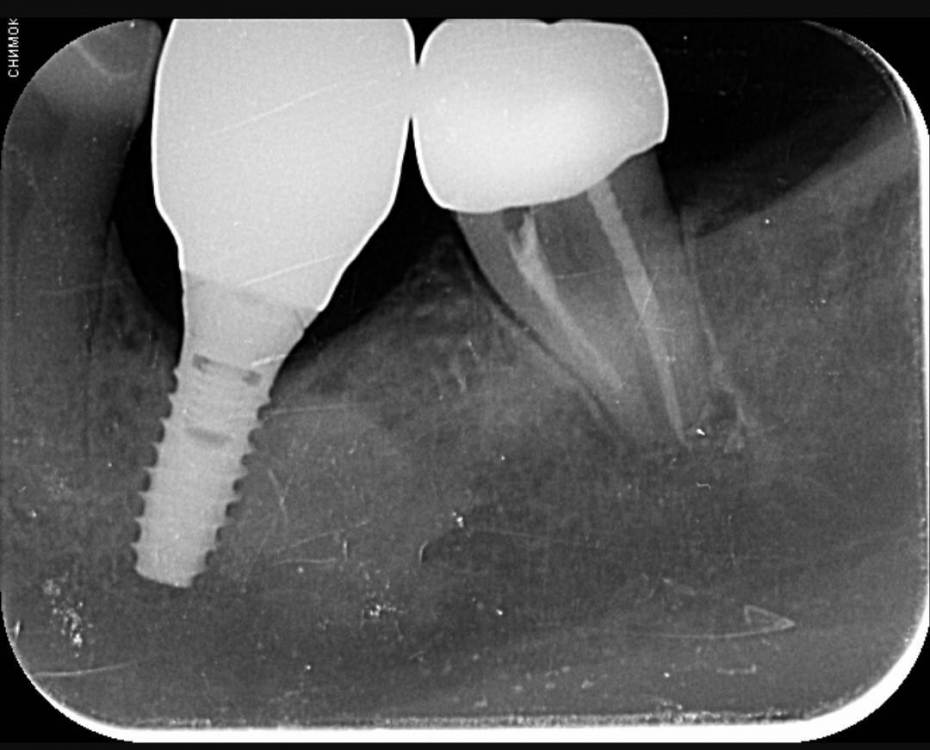

annda Опубликовано 24 ноября, 2022 Автор Поделиться Опубликовано 24 ноября, 2022 Докрутила. 1 Ссылка на комментарий

Mailze Опубликовано 28 ноября, 2022 Поделиться Опубликовано 28 ноября, 2022 24.11.2022 в 16:51, annda сказал: Докрутила. Красота! И периодонтальная связка на дистальном отличная стала! Ссылка на комментарий

Fin Опубликовано 28 ноября, 2022 Поделиться Опубликовано 28 ноября, 2022 (изменено) Отлично, какой торк был на винте когда докручивали?Если торк маленький (меньше 20) я бы предложил вам ещё раз проверить. Изменено 28 ноября, 2022 пользователем Fin Ссылка на комментарий

annda Опубликовано 28 ноября, 2022 Автор Поделиться Опубликовано 28 ноября, 2022 Где- то с 25 начался. Ссылка на комментарий